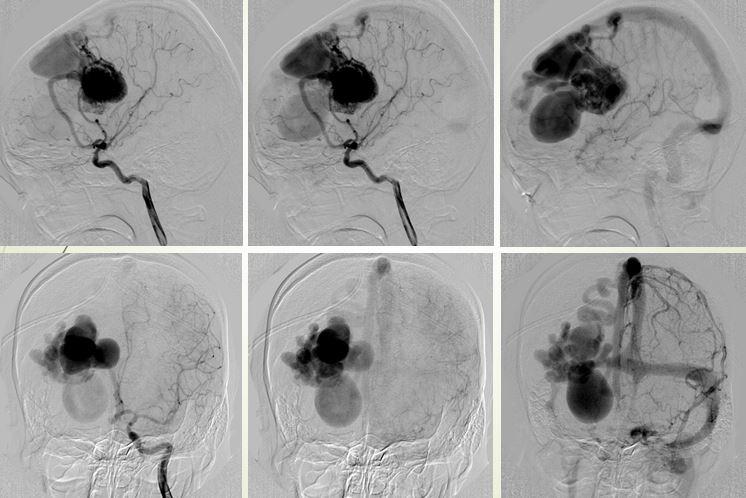

Một trường hợp khác được BS Trần Chí Cường can thiệp năm 2007 là một bé gái 14 tuổi, thường xuyên bị đau đầu, ngất xỉu khi gắng sức, động kinh toàn thể trong thời gian dài không được chẩn đoán và điều trị dị dạng thông động tĩnh mạch não bẩm sinh.

Dị dạng thông động tĩnh mạch não bẩm sinh AVM-AVF

Trường hợp này khiến BS Cường phải suy nghĩ nhiều đêm, cuối cùng tìm ra phương pháp double catheter, giống như “đắp đập” từ từ để giảm dòng chảy. Kỹ thuật này sau đó đã được áp dụng điều trị thành công cho nhiều bệnh nhân khác, BS Cường cũng báo cáo với thế giới và được ghi nhận là một kỹ thuật can thiệp nội mạch thuộc bản quyền của bác sĩ Việt Nam, được các nước học hỏi.

Hình ảnh DSA thực hiện kỹ thuật double catheter

Kỹ thuật double catheter được BS Trần Chí Cường ví von với việc đắp đập chặn dòng chảy sông Mekong